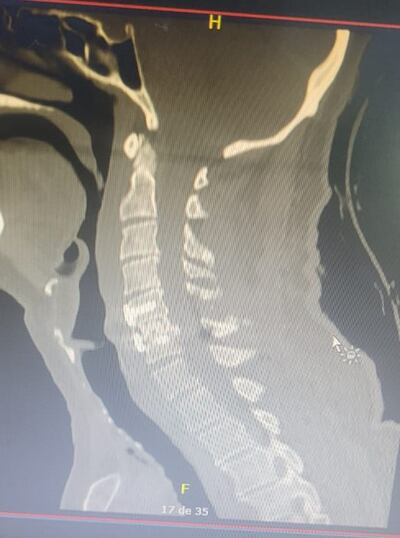

Un paciente de 70 años, víctima de un accidente de tránsito, fue sometido a una artrodesis cervical de doble vía tras presentar una luxación C5-C6 con compresión medular. Con la misma, se logró impedir que el paciente quede en silla de ruedas.

“Esta fue una fractura altamente inestable cervical, que si el paciente se movía en la cama o caminaba, en días estos casos se quedan sin poder mover las piernas”, indicaron los especialistas.